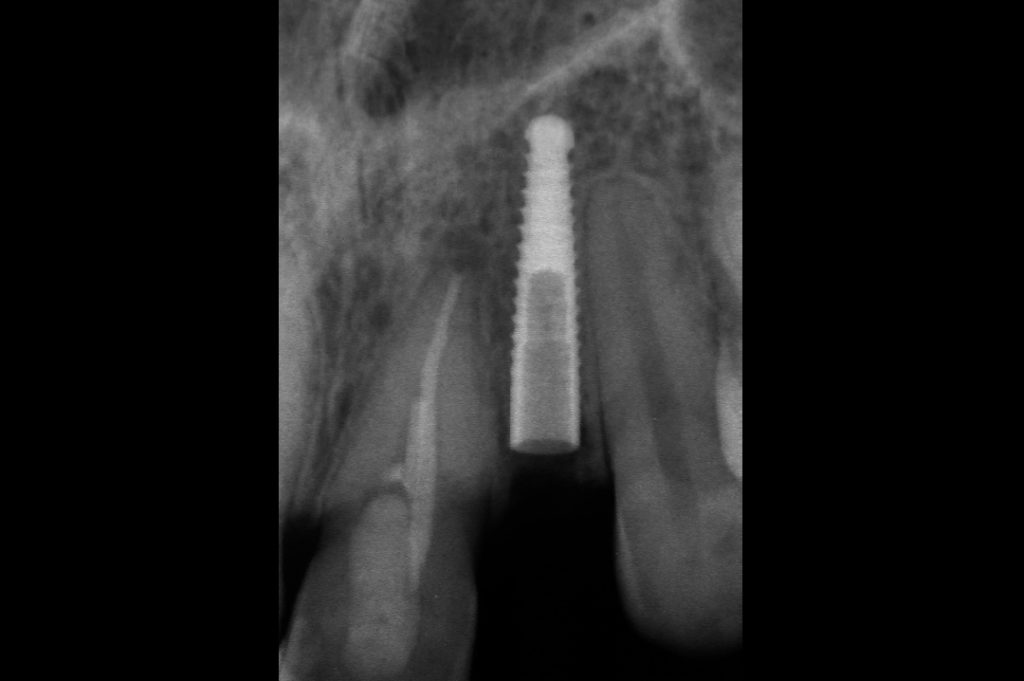

X-ray immediately after surgery to confirm correct implant positioning